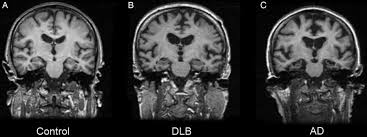

Lewy body dementia is typically diagnosed after other conditions are ruled out and the person's symptoms best fit with the diagnostic criteria for lbd. Related online courses on physioplus. Lewy body dementia stage 2 possibilities. Ct and mri show no characteristic changes in lewy body dementia but can initially help rule out other causes of dementia. Many people also experience changes in alertness including daytime sleepiness, confusion or staring spells. Read about the symptoms and what can help. Dementia with lewy bodies appears to be the second most common form of dementia, accounting for about one in five cases. Lewy body dementia, also known as dementia with lewy bodies, is the second most common type of progressive dementia after alzheimer's disease dementia.

Lewy, the scientist who discovered them. Loss of substantia nigra hyperintensity on 7 tesla mri of parkinson's disease, multiple system atrophy, and progressive supranuclear palsy. Besides nuclear imaging methods, the clinical utility of structural neuroimaging with magnetic resonance imaging (mri) for differential comparison between dementia with lewy bodies and alzheimer's disease. You also might see things that aren't there, called hallucinations. Lbd is a term that covers two conditions that have similar. Protein deposits, called lewy bodies, develop in nerve cells in the brain regions involved in thinking, memory and movement (motor control). Certain nuclear scans of the brain, including positron emission. How is lewy body dementia (ldb) diagnosed? Dr michael firbank discusses his study using functional mri in lewy body dementia and alzheimer's disease at the newcastle university institute. Focal atrophy in dementia with lewy bodies on mri: Memory loss is not always an early symptom. Lewy body dementia (lbd) is a type of progressive dementia. Many people also experience changes in alertness including daytime sleepiness, confusion or staring spells.

Lewy, the scientist who discovered them. These deposits, called lewy bodies, affect chemicals in the brain whose changes, in turn, can lead to problems with thinking, movement, behavior, and mood. Many people also experience changes in alertness including daytime sleepiness, confusion or staring spells. Mri can show loss of brain cells (atrophy), but this occurs with other types of dementia too. Lewy body dementia stage 2 possibilities.

By this point, most caregivers are worried that something is seriously wrong and seek medical attention. These deposits, called lewy bodies, affect chemicals in the brain whose changes, in turn, can lead to problems with thinking, movement, behavior, and mood. Many people also experience changes in alertness including daytime sleepiness, confusion or staring spells. In lbd, protein deposits build up in the brain. Lewy body dementia (lbd) is a type of progressive dementia that leads to a decline in thinking, reasoning and independent function because. Dementia with lewy bodies or lewy body dementia is dementia caused by the presence of lewy bodies in the brain. Lewy body dementia (lbd) is often regarded as the second most common dementia in older individuals after alzheimer disease,1,2 possibly sharing the. Memory loss is not always an early symptom. How is lewy body dementia (ldb) diagnosed? Lewy body dementia symptoms include recent loss of memory, difficulty concentrating or paying attention, misperceptions of space and time. The deposits are called lewy bodies and are named after friedrich h. Mri can show loss of brain cells (atrophy), but this occurs with other types of dementia too. Protein deposits, called lewy bodies, develop in nerve cells in the brain regions involved in thinking, memory and movement (motor control).